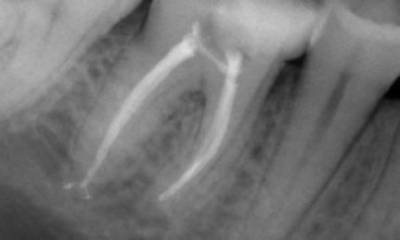

Before: Upon examination, there was a caries lesion related to the lower right first molar. Radiographic examination revealed proximity of the lesion to the pulp horn and combining it with the chief complaint, a final diagnosis of chronic irreversible pulpitis was concluded.